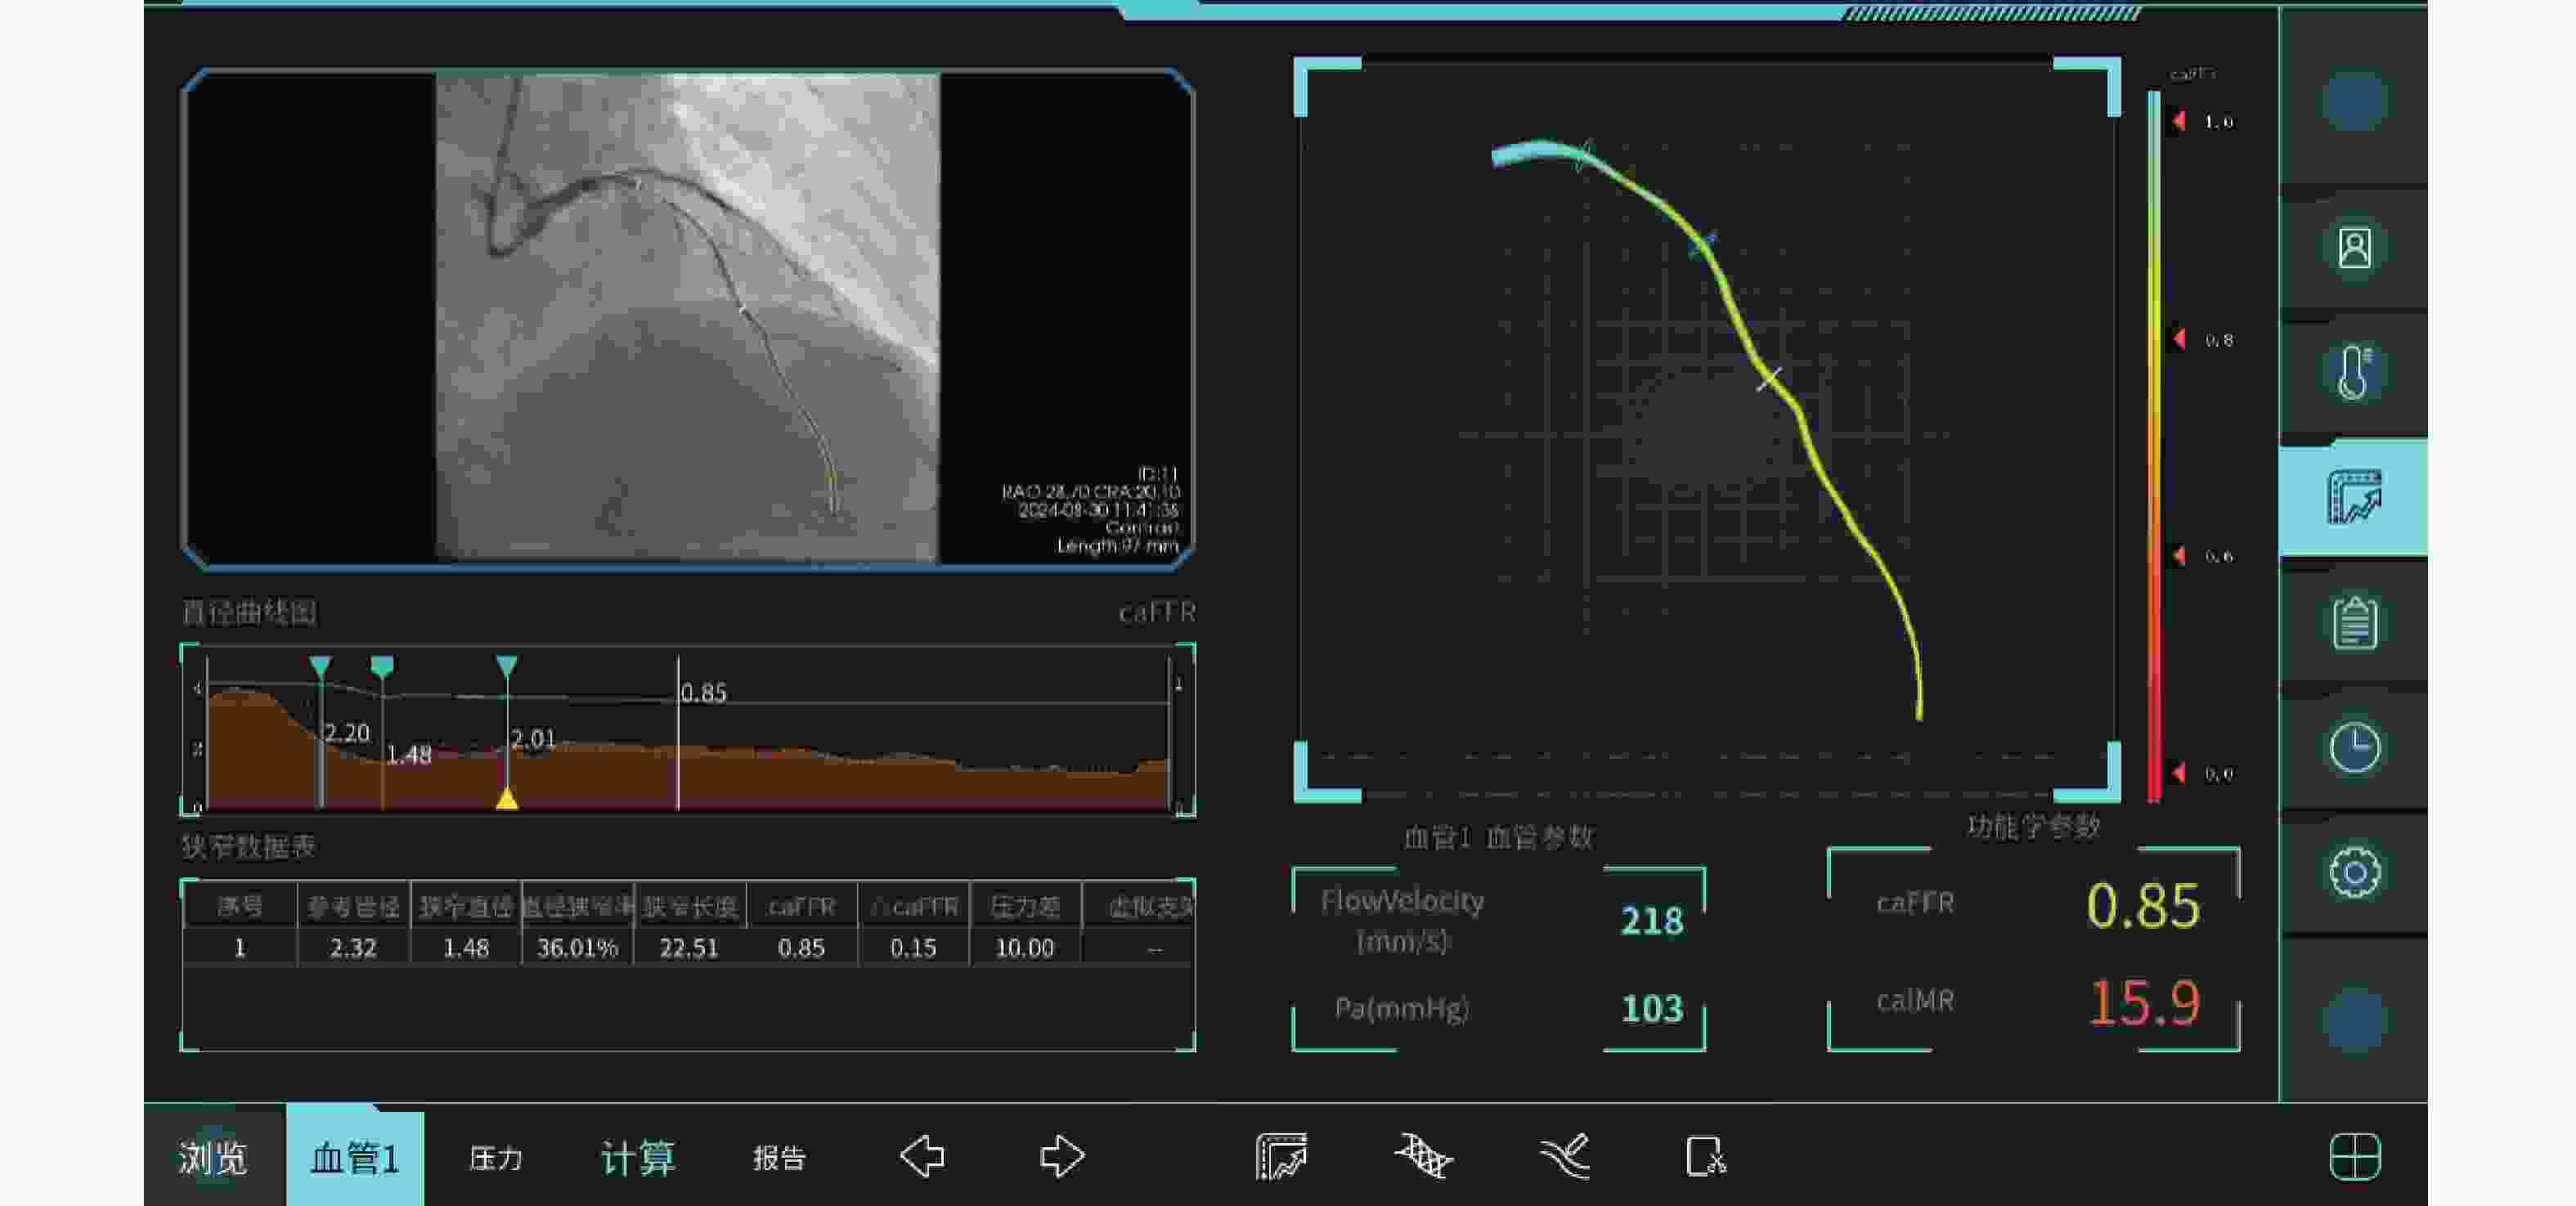

目的 通过心脏磁共振评估基于冠状动脉造影的微循环阻力指数对于冠状动脉微循环障碍的诊断效能,并进一步探究冠状动脉微循环障碍与无症状脑梗死间的相关性。 方法 选取2021年1月至2024年12月期间就诊于昆明医科大学第二附属医院心血管内科的患者231例。通过FlashAngio系统对冠状动脉造影图像左前降支血管进行分析得出caIMR值,以25为界限分为冠状动脉微循环正常组(caIMR<25,n = 126)和冠状动脉微循环障碍组(caIMR≥25,n = 105)。收集所有患者的一般临床资料、实验室指标(血常规、生化全套、糖化血红蛋白)、颅脑CT/MRI结果、心肌微循环磁共振灌注参数(达峰时间(tpeak)、相对峰值信号强度(RSIpeak)、最大上升斜率(Slopemax))、经胸超声心动图常规参数。 结果 (1)50例同时完善CMR和caIMR的患者, caIMR≥25组左前降支支配区域出现了不同程度的tpeak延长,RSIpeak和Slopemax降低,表明caIMR≥25组存在冠状动脉微循环障碍。进行Cohen's Kappa检验一致性分析, Kappa值0.839(P < 0.05),表明caIMR对于CMD的识别具有较高的准确度和评价效果;(2)127例糖尿病患者按照糖化血红蛋白(HbA1c)水平分为血糖控制良好组(4%≤HbA1c<6%)、血糖控制不佳组(6%≤HbA1c<8%)、血糖控制差组(HbA1c≥8%)。40例血糖控制良好组、59例血糖控制不佳组及28例血糖控制差组患者对比,血糖控制不佳组和血糖控制差组caIMR值中位数均高于血糖控制良好组(P < 0.05),且血糖控制不佳组caIMR中位数24.60接近于诊断冠状动脉微循环障碍的caIMR分界值25,血糖控制差组caIMR中位数32.15远高于分界值25;(3)在冠状动脉微循环障碍组中发现很多患者同时存在无症状脑梗死,而在冠状动脉微循环正常组患者中则较少,差异具有统计学意义(P < 0.05)。进一步进行Phi系数相关性分析,Phi系数0.562,差异具有统计学意义(P < 0.001)。提示冠状动脉微循环障碍与无症状脑梗死之间存在相关性。 结论 caIMR对于冠状动脉微循环功能障碍的识别具有较高准确度,且与心脏磁共振的评估效能一致性较高,而在冠状动脉微循环障碍的患者中发现大多同时存在无症状脑梗死,说明心脑微血管两者之间的病变发展可能存在相关性。 Abstract:Objective To evaluate the diagnostic efficacy of coronary angiography-based microcirculatory resistance index for coronary microcirculatory dysfunction through cardiac magnetic resonance (CMR), and further explore the correlation between coronary microcirculatory dysfunction and silent cerebral infarction. Methods 231 patients from the Cardiovasology Department of the Second Affiliated Hospital of Kunming Medical University between January 2021 and December 2024 were selected. The caIMR value of the left anterior descending coronary artery was analyzed using the FlashAngio system, with patients divided into normal coronary microcirculation group (caIMR<25, n = 126) and coronary microcirculatory dysfunction group (caIMR≥25, n = 105). General clinical data, laboratory indicators (complete blood count, biochemical panel, glycated hemoglobin), cranial CT/MRI results, cardiac microcirculatory perfusion MRI parameters (time to peak [tpeak], relative signal intensity at peak [RSIpeak], maximum upslope [Slopemax]), and routine transthoracic echocardiography parameters of all patients were collected. Results (1) Among 50 patients who completed both CMR and caIMR, the caIMR≥25 group showed varying degrees of tpeak prolongation, with reduced RSIpeak and Slopemax, indicating coronary microcirculatory dysfunction. Cohen's Kappa consistency analysis showed a Kappa value of 0.839 (P < 0.05), suggesting high accuracy of caIMR in identifying CMD; (2) 127 diabetic patients were categorized based on HbA1c levels into good glycemic control group (4%≤HbA1c<6%), moderate glycemic control group (6%≤HbA1c<8%), and poor glycemic control group (HbA1c≥8%). Comparing 40 patients in the good control group, 59 in the moderate control group, and 28 in the poor control group, the median caIMR values in the moderate and poor control groups were higher than the good control group (P < 0.05). The moderate control group's median caIMR of 24.60 was close to the diagnostic threshold of 25, while the poor control group's median caIMR of 32.15 was significantly higher; (3) In the coronary microcirculatory dysfunction group, several patients simultaneously had silent cerebral infarction, which was less common in the normal microcirculation group, with statistically significant difference (P < 0.05). Further Phi coefficient correlation analysis showed a coefficient of 0.562, with statistically significant difference (P < 0.001), suggesting a correlation between coronary microcirculatory dysfunction and silent cerebral infarction. Conclusion caIMR demonstrates high accuracy in identifying coronary microcirculatory dysfunction, with good consistency with CMR assessment. The high prevalence of silent cerebral infarction in patients with coronary microcirculatory dysfunction suggests potential interconnected pathological development in cerebral and cardiac microvascular systems. -

Table 5. Comparison of coronary physiological indicators between the normal coronary microcirculation group and the coronary microcirculation dysfunction group[($ \bar x \pm s $)/M(P25,P75)

项目 冠状动脉微循环正常组(n=126) 冠状动脉微循环障碍组(n=105) U P 冠状动脉参考管腔 2.47±0.57 2.43±0.51 6854.500 0.530 冠状动脉狭窄直径 1.61±0.45 1.59±0.41 6488.500 0.930 冠状动脉直径狭窄率 0.34(0.23,0.43) 0.32(0.25,0.42) 6762.000 0.772 冠状动脉狭窄长度 14.15(9.08,19.49) 12.33(8.41,16.87) 7279.500 0.189 冠状动脉内压力差 4(2.00,11.75) 3(2.00,7.00) 7688.000 0.133 表 6 冠状动脉微循环障碍的多因素Logistic回归分析